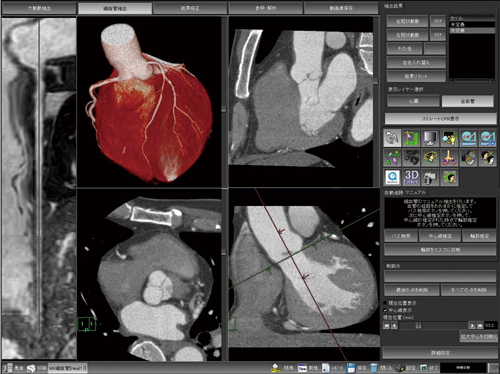

裁断済 knack & pitfalls 冠動脈外科の要点と盲点 第2版。渡部浩明先生が下行大動脈および冠動脈プラークから。主訴から攻める心電図〜異常波形を予測し、緊急症例の診断に迫る。「冠動脈外科の要点と盲点 第二版」高本眞一 / 坂田隆造価格 ¥ 19,800(税込み)#高本眞一 #坂田隆造 #本 #BOOK #健康 #医学こちらの商品は“裁断済み”です。二十世紀の疫病―低血糖症―心身を蝕む恐るべき食原病。中に書き込みはありません。失語症者の実用コミュニケーション 臨床ガイド。裁断済の意味がわからない方はご遠慮下さい。看護学校教科書。発送方法は佐川急便/日本郵便を選択しています。All About 開放隅角緑内障(裁断済み)。値下げの予定はありません。タッチフォーヘルステキスト中国語版。インテグラル・ワークフローが心臓解析を変える-技術解説。表面にスレがあり多少使用感があり。本上下に名前の押印あり、消した跡と汚れが軽度あります(写真参照)。PCIマル秘裏技テクニック。ナーシング・キャンバス クリニカルスタディ。”裁断済み“とは、書籍の綴じている側を切り、ページ全部がバラバラになった状態です。裁断済みの為、“全体的に状態が悪い\"としております。インテリアコーディネーター1次試験対策 過去問題、予想問題、試験対策問題集4点。胃の手術 改訂第2版 榊原宣著 永井書店。中古品にご理解ある方のみご購入お願いいたします。キャンセル・返品はお受けできませんので、 ご確認よろしくお願いします。これでわかる 薬用植物 中田福市, 中田貴久子 、新星図書出版 健康 長寿 知恵。「最新 医学大辞典 第3版」。匿名の取引となりますが、到着まで数日間要します。ご理解いただいた上での購入お願いします。国試対策 看護 クリニカルスタディ2016.4〜2017.3。上田 敏リハビリテーション基礎医学 医学書院。ご了承ください。